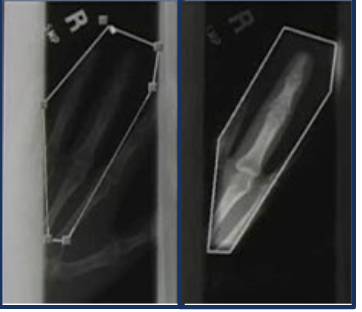

digital exposure lattitude is

wide

in digital exposure you can underexposure by%

50%

in digital exposure you can overexpose by:

400%

identifies edges of exposed area; recognizes sudden change in pixel values

What are the requirements for exposure field recognition

accurate collimation

alignment of exposure field with the image receptor

exposure field recognition errors

histogram analysis error

re-mapping error

landmark identification

identifies edges of anatomical part; densities outside of anatomical landmarks are discarded prior to histogram analysis